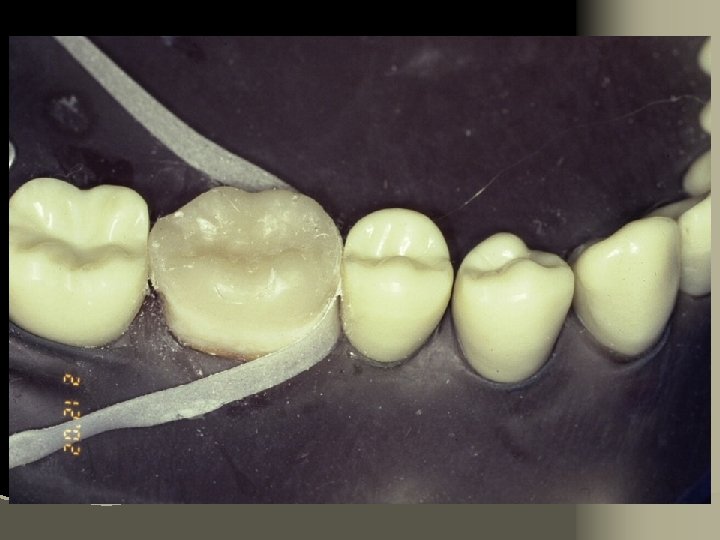

Cementation Procedure 1. Remove temporary and all residue of temporary cement 2. Check occlusion on adjacent teeth (mylar shimstock and articulating paper) 3. Place rubber dam 4. Clean tooth with pumice and rubber cup, rinse and lightly dry 5. Try in restoration for fit.

6. Adjust proximal contacts if necessary 7. Evaluate shade intraorally using water soluble try-in paste (optional) 8. Rinse out try-in paste and air dry 9. Etch inside of restoration (HF porcelain etchant X 2 minutes), rinse with distilled water and air dry 10. Place drop of silane (porcelain primer) on intaglio surface for 1 minute, lightly air thin to evaporate solvent

11. Place matrix to protect adjacent teeth from etchant 12. Etch prepared tooth surfaces (phosphoric acid). Rinse and lightly air dry 13. Apply prime/bond for 15 seconds 14. Air thin for 3 seconds – AVOID POOLING 15. Light cure for 20 seconds per surface